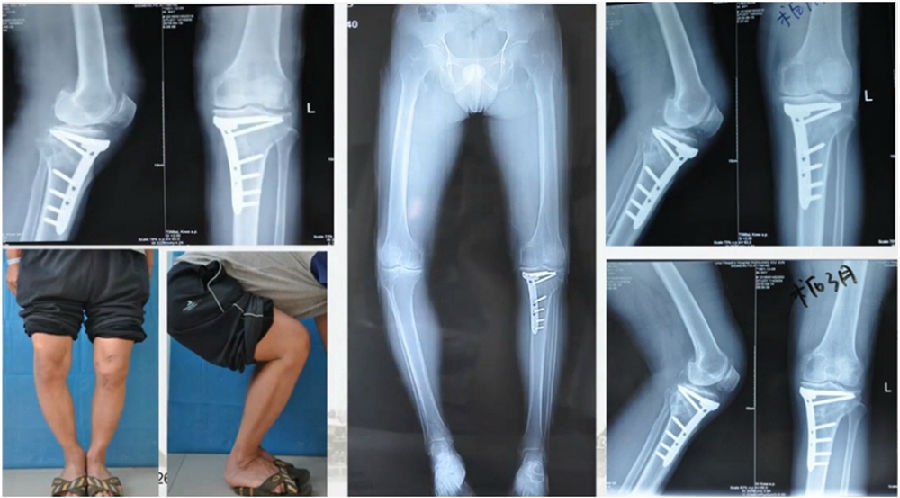

典型病例,男性,65岁,农民,双膝内翻16度。

术前影像

第一次为该患者做了传统上行开放截骨,撑开角度较大,术后用三种方法测量髌骨高度,发现髌骨高度受到影响,髌骨变低了。

左膝上行OWHTO(初次)

上行OWHTO髌骨高度测量

ISI法测量髌骨无明显变化;CDI、BPI法测量髌骨降低明显;患者屈膝锻炼困难。

第二次来院做另一侧肢体时,采用下行截骨,术后患者髌骨高度,无论用哪种方法测量都无明显变化,而且患者膝关节功能迅速得到恢复。

右膝下行OWHTO(再次)

下行OWHTO髌骨高度测量

ISI法测量髌骨无明显变化;CDI、BPI法测量髌骨无明显变化;患者屈膝明显改善。